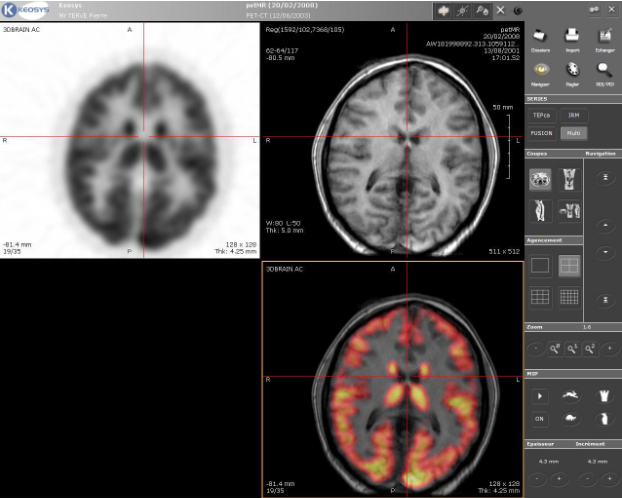

- Ver (Imagen): Técnicas como la Imagen por Resonancia Magnética (IRM) o el ultrasonido proporcionan un mapa 3D en vivo del interior del cuerpo. Estas imágenes permiten localizar tanto la anatomía del paciente (un tumor, un coágulo) como la flota de nanobots.

- Pensar (IA): El flujo de imágenes alimenta a los algoritmos de IA. Modelos de machine learning identifican el objetivo y calculan la trayectoria óptima para llegar a él. Algoritmos más avanzados, como el aprendizaje por refuerzo profundo (Deep Reinforcement Learning), pueden entrenar al «piloto» de IA para navegar por entornos complejos y dinámicos como el flujo sanguíneo, aprendiendo a «nadar» contra la corriente o aprovecharla.

- Actuar (Campos Magnéticos): La trayectoria calculada por la IA se traduce en comandos precisos para el sistema de propulsión, por ejemplo, ajustando las bobinas electromagnéticas miles de veces por segundo para guiar a los nanobots magnéticos por la ruta planificada.

Escáner PET-MRI cerebral fusionado, destacando regiones de alta actividad metabólica (en rojo y amarillo) By Mco44 – Own work, Public Domain, https://commons.wikimedia.org/w/index.php?curid=3587922